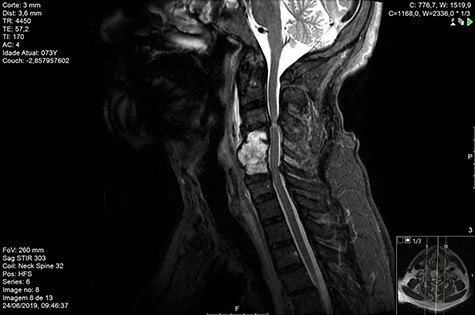

MRI and CT scans performed at 90 days post-radiation therapy showed an arrest of further progression of instability and resolution of the lytic lesion (Figs 7–13).